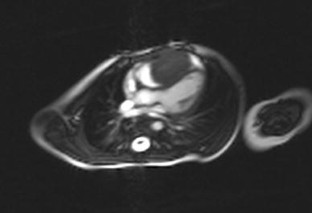

Cardiac fibromas are extremely rare in the general pediatric population and may present with a wide spectrum of clinical signs, including life-threatening arrhythmias and sudden death. We report a 14-month-old boy who presented with failure to thrive as the only symptom. Echocardiography showed a large cardiac fibroma in the right ventricle. Cardiac magnetic resonance imaging confirmed the diagnosis. After complete surgical tumor resection, the boy showed normal catch-up growth. This case underlines the diversity of clinical features of cardiac tumors, which implies that they should be considered early in the differential diagnosis of infants with failure to thrive.

Fig. 2